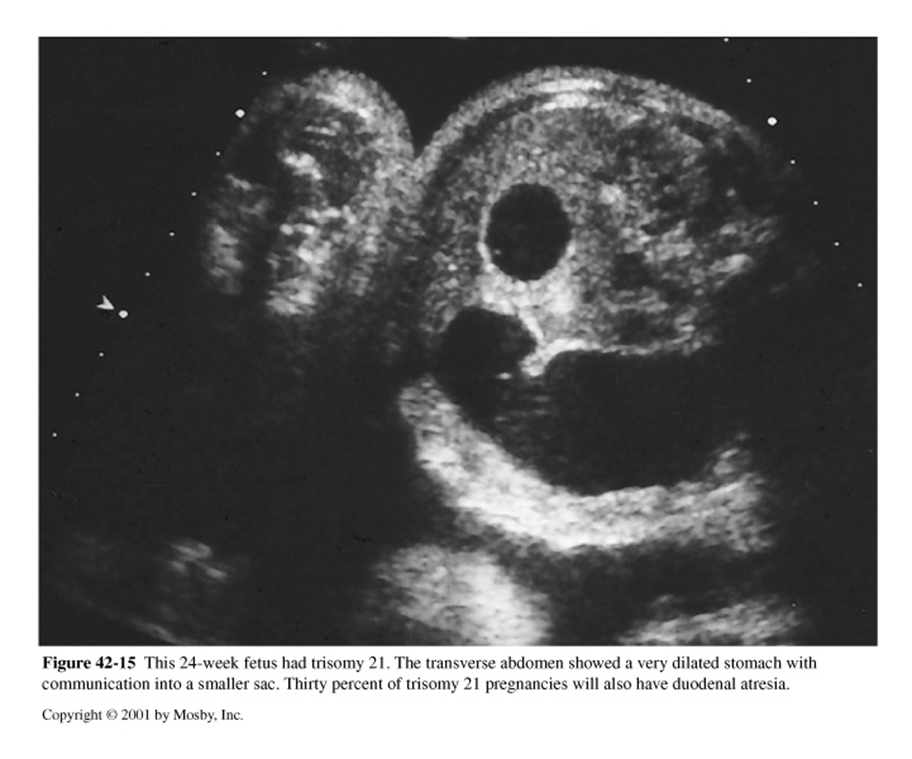

What is this image showing?

duodenal Atresia

Duodenal atresia may coexist with ______ ________ and 30% will have ________ ___

Annular pancreas

Trisomy 21